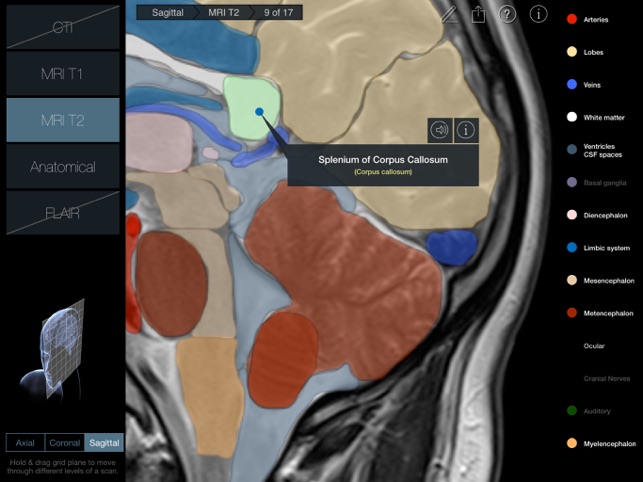

170 images in 3 planes with 2 scan types for each plane (a third for the Axial plane) and anatomical slices for each plane.

•MRI T2 (Turbo Spin Echo T2-weighted Magnetic Resonance Imaging)

A 3D plane (Axial, Coronal or Sagittal) is pulled or pushed through a 3D head to navigate through the 17 scans in that plane.

300 individual structures labeled along with descriptions and voice over pronunciations.

Individual structures are grouped into 14 categories and each category can be turned on or off to allow for clearer identification of structures.

Each scan and slice is anatomically identical, so every labeled structure is in the same position in every image and scan – this makes it much easier to identify variances in appearance of structures between scans.

•Latin nomenclature for each anatomical structure

•Detailed descriptions included